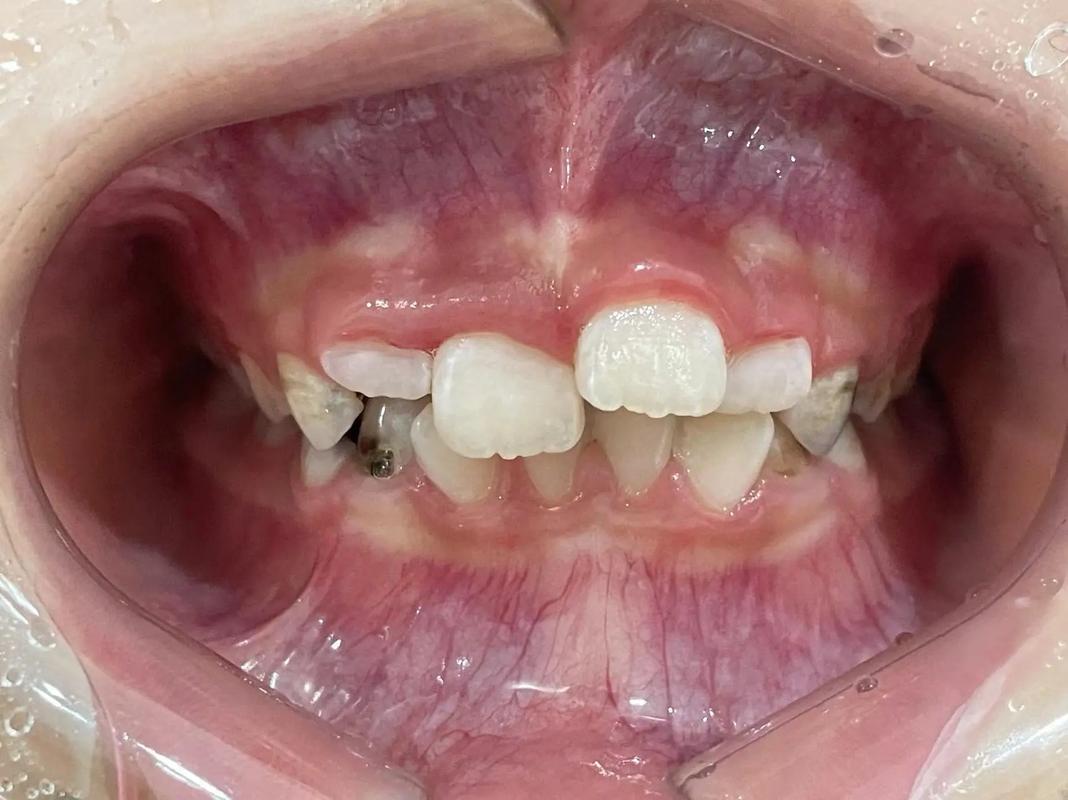

(图片来源网络,侵删)- 原因: 少数人(个体差异)在牙齿移动过程中,牙根尖端可能会发生轻微的吸收(牙根变短),这种吸收通常是轻微的,不影响牙齿的稳固性和使用寿命,但在极少数情况下,如果吸收比较严重,可能会降低牙齿的长期稳固性。

(图片来源网络,侵删)- 原因: 成年人通常比青少年更容易存在牙周问题(牙龈退缩、牙槽骨吸收),如果牙周状况不佳,风险相对较高,青少年牙周组织健康、修复能力强,风险相对较低。